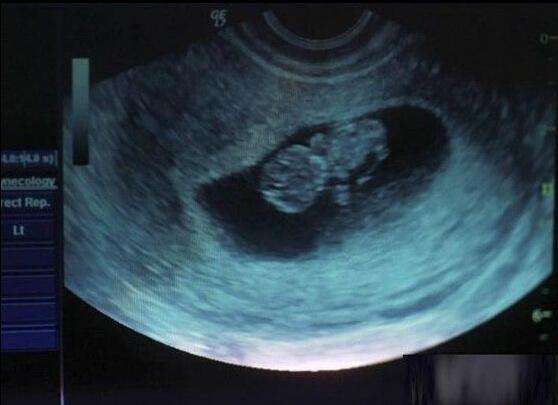

小莉的老公很发愁,小莉今年21岁,已经和老公备孕有一年多了,还是没有怀上宝宝,而且月经也很不规律。

老公担心小莉有什么疾病,尽管小莉很不情愿,但还是强拉着小莉来到医院做检查,医生发现小莉子宫宫腔粘连得非常严重,经过反复询问,小莉终于说出了自己之前已经做过4次人流的事实。